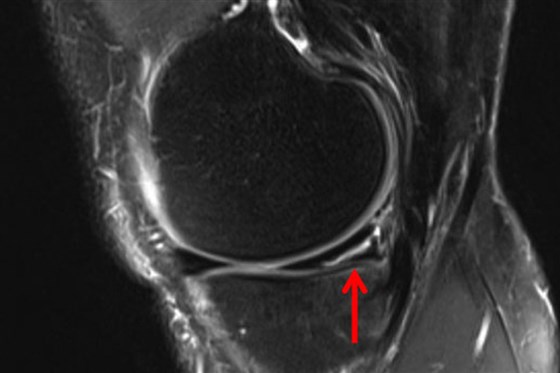

Mithilfe einer MRT-Untersuchung kann man das Knie unter der Lupe nehmen und Klarheit schaffen. Nach 20-30 Minuten in der MRT-Röhre, kann der Arzt sehen, ob der Meniskus nur angerissen hat oder komplett in Fetzen liegt oder sogar verschoben ist.

Im Vergleich zum Röntgenbild, das nur Knochen zeigt, sieht die MRT alles: Bänder, Knorpel und auch den Meniskus. So weiß der Arzt sofort, ob die Verletzung ernst ist oder ob man mit ein paar Übungen wieder fit wird.

Meniskusriss - für den Fachmann im MRT eine leicht erkennbare Verletzung.

Ein Meniskusriss ist kein K.-o.-Schlag, aber ohne die notwendige Behandlung kann er das Fußballer-Leben zur Hölle machen. Dank der MRT kann der Schweregrad der Meniskusverletzung sehr gut eingeschätzt werden und die richtige Behandlung unmittelbar eingeleitet werden, sodass schnellstmöglich eine Rückkehr auf dem Platz ermöglicht wird.